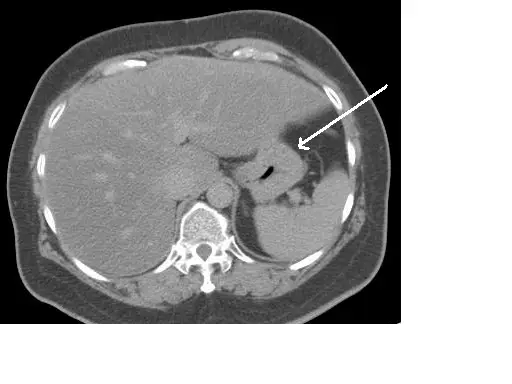

下圖中之影像箭號所示最可能為何? 圖片

本圖為腹部軸切面 CT(非增強或增強掃描),顯示上腹部橫斷面影像。影像中可見以下主要結構:

• 右側(患者左側顯示在影像右方):肝臟(liver)佔據右上腹大部分空間,呈均勻中等密度。

• 左上腹:脾臟(spleen)呈均勻軟組織密度,位於左側肋下。

• 中央偏左:一個含有低密度氣體(空氣)的管腔構造,壁為軟組織密度,箭號指向此結構——此即(stomach),可見其胃腔內有氣體影,胃壁清晰可辨。

• 脊椎:椎體位於影像正中央偏後,旁有主動脈與下腔靜脈。

• 胰腺:可見於脊椎前方偏左之軟組織構造。

白色箭號指向的位置在左上腹、脾臟前內側、肝臟左葉後方,此位置正是胃體(gastric body)或胃底(gastric fundus)的典型 CT 位置。胃腔內氣體造成的低密度區域,加上周圍的軟組織胃壁,是辨識胃的重要特徵。

(A) stomach(胃)正確答案

胃位於左上腹,其 CT 特徵包括:腔內含氣體(黑色低密度)或液體、胃壁為軟組織密度、位